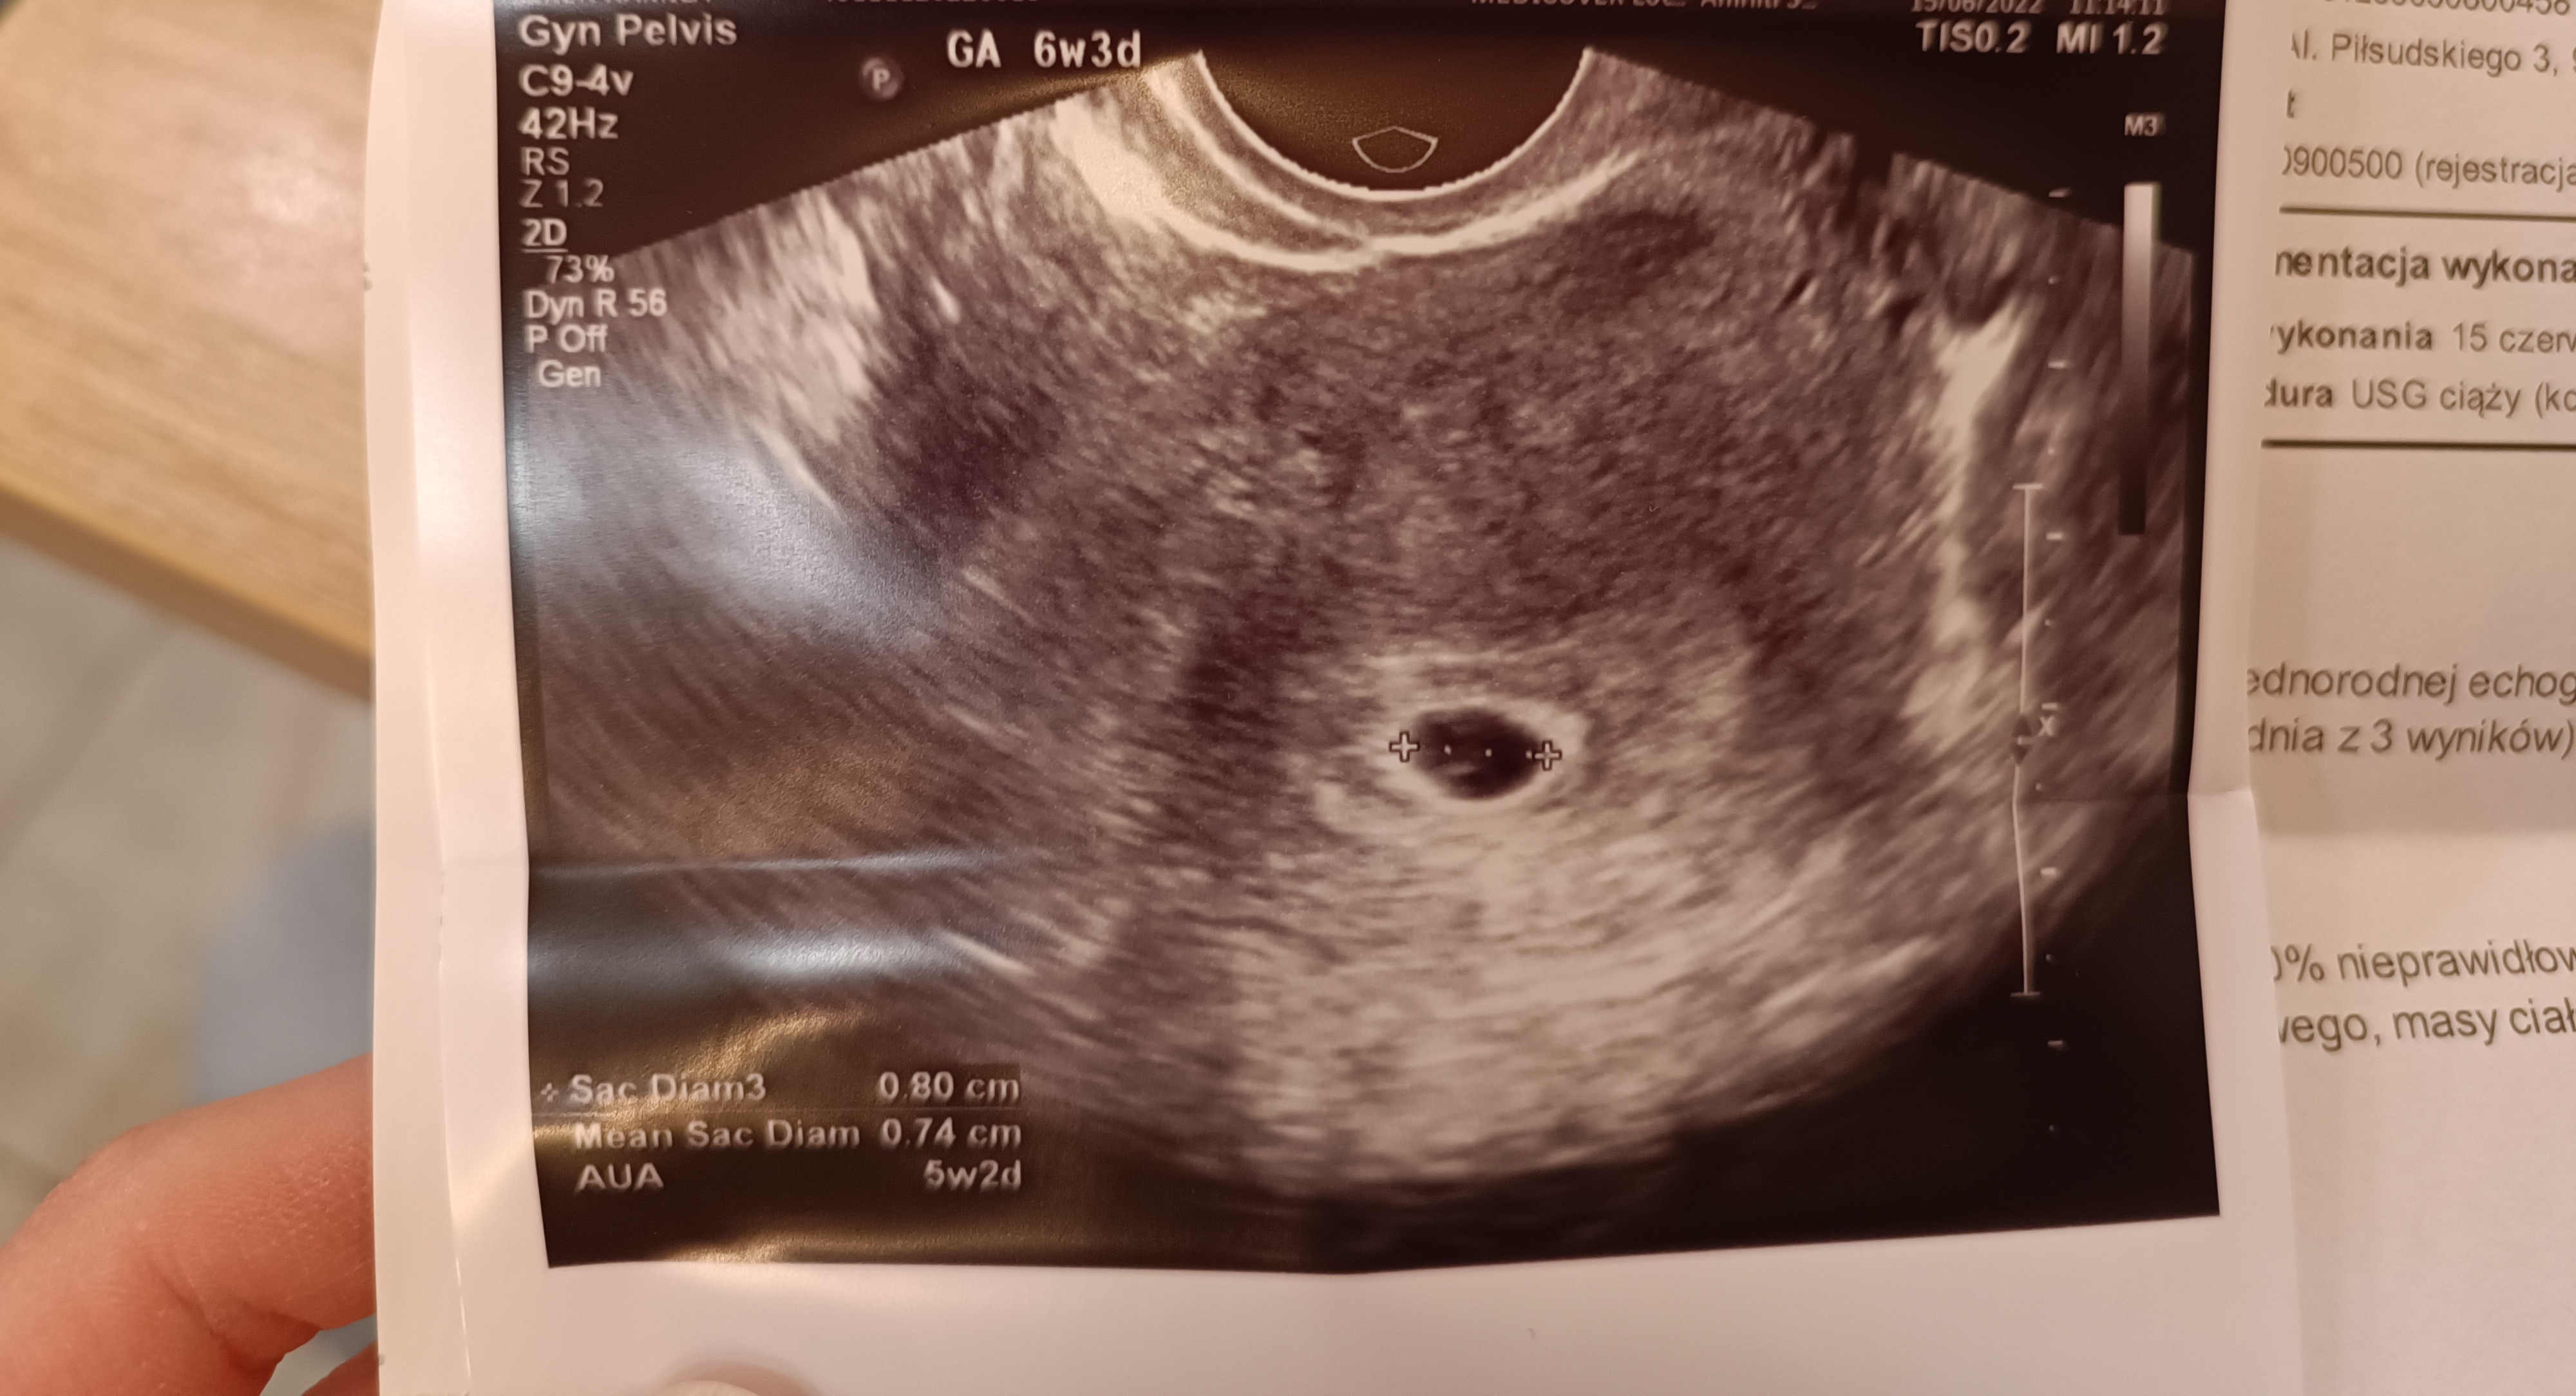

Ja tu widzę pęcherzyk ciążowy i pęcherzyk zoltkowy czyli taka spiżarnia dla maluchaDziewczyny czy na moich zdjęciach widać zarodek?

Byłam na usg w pon wg om 6w1d wg usg 6w3d

Dajcie znać czy coś tam widzicie![]()